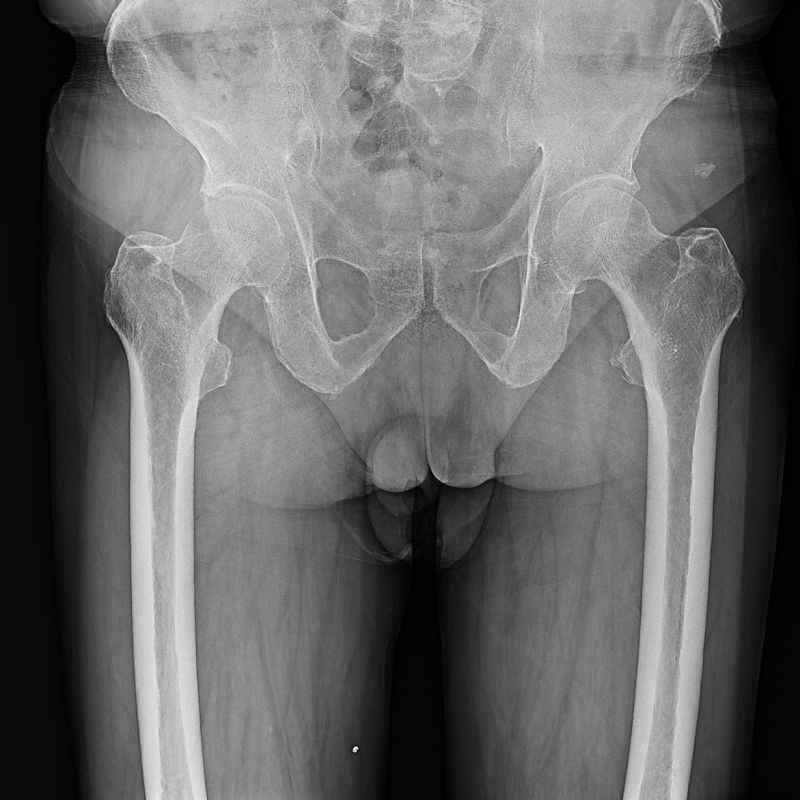

全自動(dòng)拼接

●呈現(xiàn)全下肢或全脊柱圖像

●在脊柱及下肢畸形矯正手術(shù)治療中,為術(shù)前方案制定和術(shù)后復(fù)查提供精準(zhǔn)測(cè)量

●有效解決傳統(tǒng)X光片不能一次成像問(wèn)題,為患者提供更加優(yōu)質(zhì)的醫(yī)療服務(wù)

Clinical picture

臨床圖片